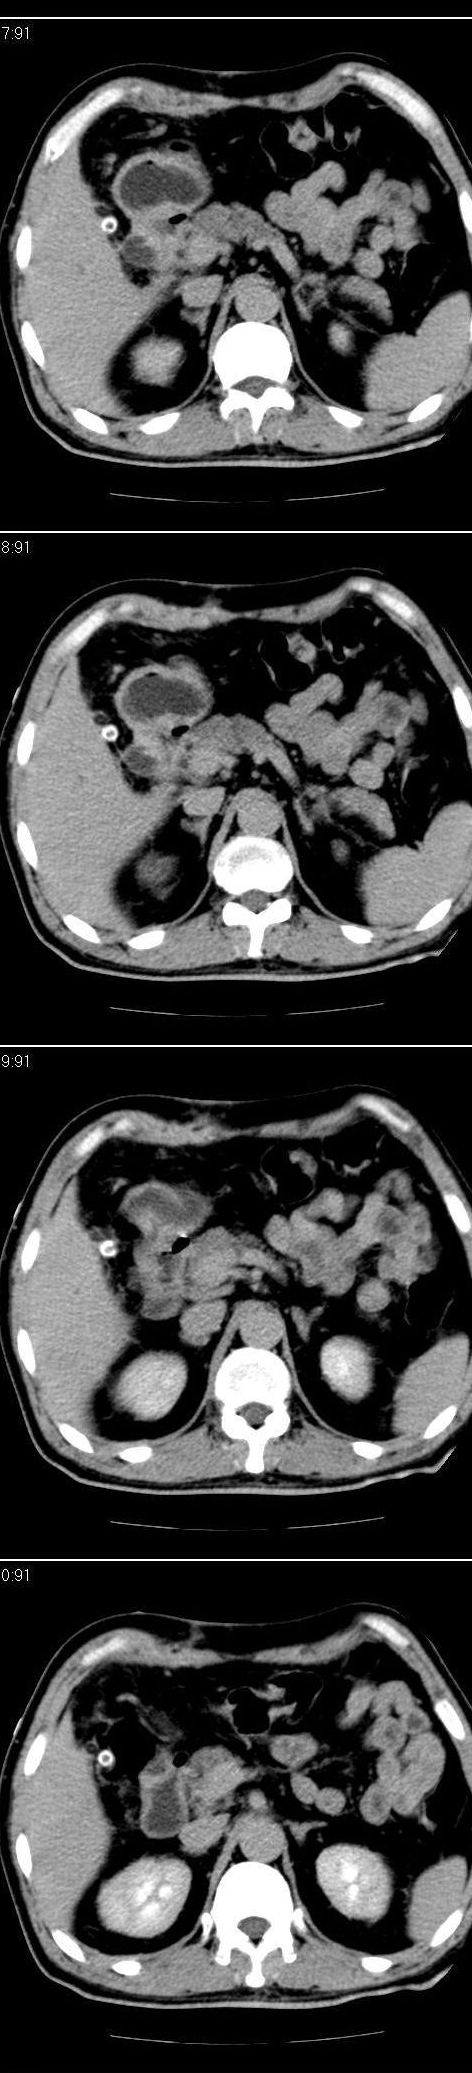

标题: CT13147:男,57岁。因胆结石阻塞性黄疸入院。 [打印本页]

标题: CT13147:男,57岁。因胆结石阻塞性黄疸入院。

男,57岁。因胆结石阻塞性黄疸入院。这是胆囊切除术后的照片,看看此片到底有什么问题。

胆总管有没有问题,尤其是肝门附近的胆总管?

肝门附近的胆总管轻度扩张 请楼主复习术前片

肝内外胆管轻度扩张,胆囊窝内见引流管考虑胆囊切除术后改变.胃窦部软组织似增厚,建议胃镜检查.

在手术切除胆囊的过程中,发现肝门部胆总管恶性占位,因为家属不同意手术,没有切除,能看出来么?

现有资料很难说,薄层可能清楚些,如临床不提供,易诊断为术后改变。

不是楼主提醒还真看不出来,肝内胆管扩张。略显僵硬。

肝内外胆管轻度扩张。楼主提示左右肝管合汇区域壁稍厚。胆总管末段壁似也稍厚有轻度强化。就现有资料诊断难。